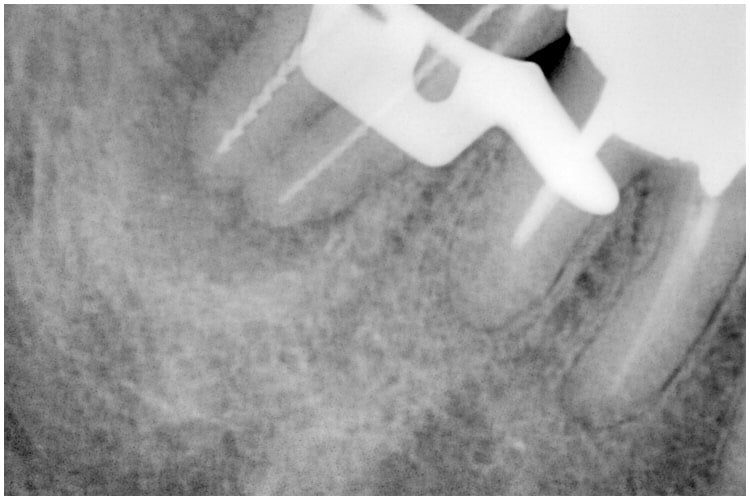

治療後

症例4 非外科 病変あり 前歯 治療後